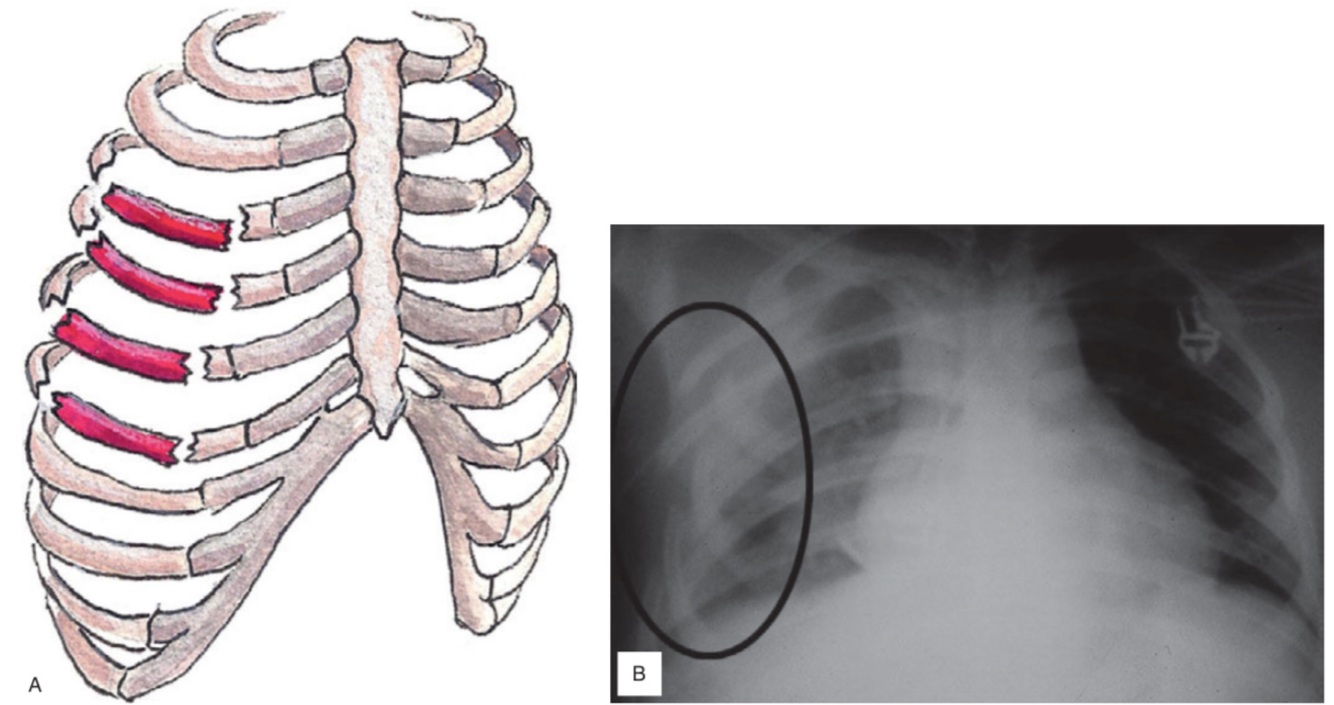

Pneumotórax Instável

Tórax instável - tratamento

Suporte oxigênio analgesia